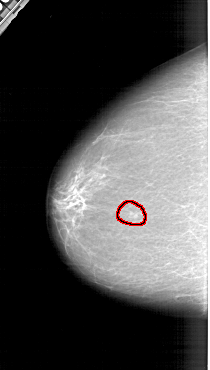

A_1308_1.LEFT_CC

LEFT_CC LINES 6286 PIXELS_PER_LINE 3556 BITS_PER_PIXEL 12 RESOLUTION 43.5 OVERLAY

FILE: A_1308_1.LEFT_CC.OVERLAY

TOTAL_ABNORMALITIES 1

ABNORMALITY 1

LESION_TYPE MASS SHAPE LOBULATED MARGINS ILL_DEFINED

ASSESSMENT 4

SUBTLETY 3

PATHOLOGY BENIGN

TOTAL_OUTLINES 1

BOUNDARY